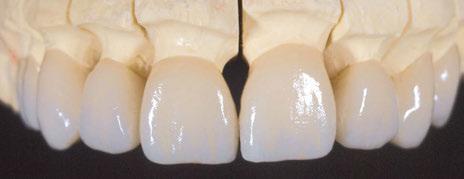

La Precisión Digital que Tu Sonrisa Merece

En Laboratorio Ceranium somos expertos en tecnología de vanguardia y nuestro equipo de técnicos trabajan juntos para garantizarte una experiencia dental incomparable.

¿Por qué debes elegirnos como tu laboratorio?

Nuestros SERVICIOS

ƒ Prótesis Fija

 Perfeccionamiento de estructuras de titanio con el nuevo servicio Tinium.

 Disilicato de Litio, Zirconio y Metal-Cerámica.

ƒ Prótesis Removible y Férulas de descarga

ƒ Cirugía Guiada

 Planificación Digital: Seguridad y exactitud en cada paso.

 Guías Quirúrgicas Personalizadas: Menor tiempo en quirófano, mejor recuperación.